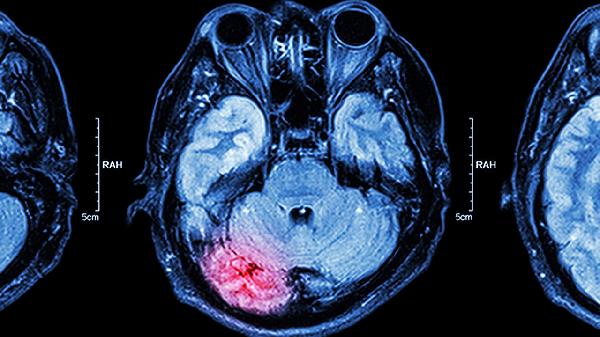

恶性肿瘤如转移瘤或胶质瘤虽占比低但进展迅速,易侵犯周围脑组织及血管,可能引起脑积水或颅内压增高,需结合放化疗等综合治疗。肿瘤若包裹重要血管或神经,手术风险显著增加,术后遗留神经功能障碍概率较高。罕见情况下肿瘤突发出血会导致意识障碍甚至呼吸骤停,需紧急处理。

发现桥小脑角区占位应及时就诊神经外科,通过MRI增强扫描明确肿瘤特征。日常需警惕突发头痛、呕吐或视力变化,避免剧烈运动以防肿瘤出血。术后患者应定期复查,配合康复训练改善神经功能缺损。